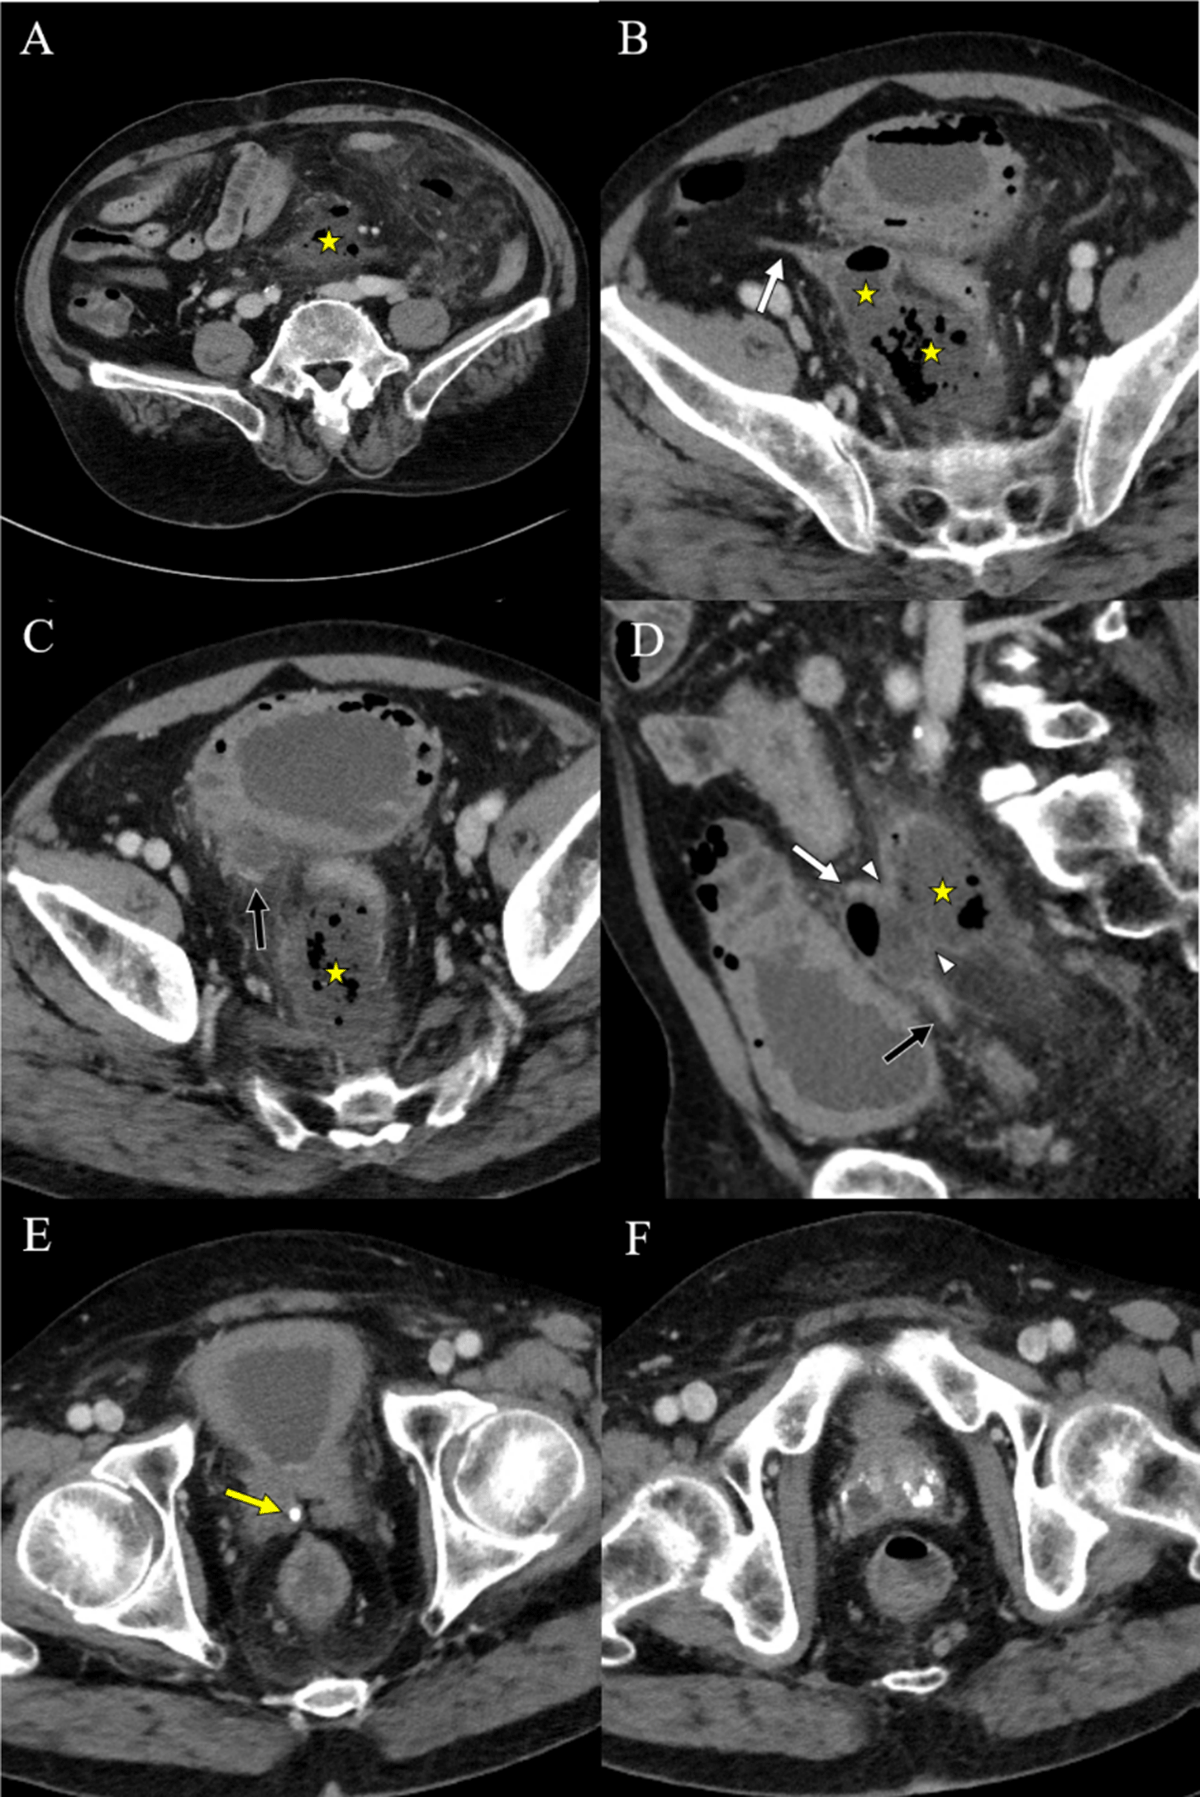

Figure 1

Pre-treatment CT images of a 65-year-old man with rupture of a vas deferens (VD) abscess. Axial and sagittal images (A–D) show a large abscess along the sigmoid mesocolon. Axial images (B, C) show the proximal and distal portion of right VD. A sagittal image (D) shows a wall defect of the VD adjacent to the abscess. An axial image (E) shows a tiny stone at the point where the VD joins the seminal vesicle. Axial images (F) show multifocal abscesses and dystrophic calcifications in the prostate. (asterisk: abscess, white arrow: proximal VD, black arrow: distal VD, arrowhead: VD wall defect, yellow arrow: VD stone).